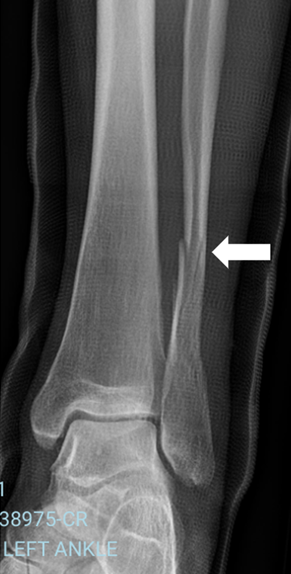

Sometimes at Flex Physio we get very unusual splinting requests. This young gentleman - a keen surfer - had been struck by a loose surfboard on the side of his leg as he duck-dived under a wave down near Margaret River 3 weeks earlier. An undisplaced fracture of the fibula was identified (See Xray image), and he was treated first in a fiberglass cast, then in a 'moon boot'. His recovery was going well, but it was mid-summer in Western Australia, and he was getting incredibly frustrated not being able to get in the water for a swim. He discussed it with his treating doctor, who suggested we might be able to come up with a waterproof solution for him.